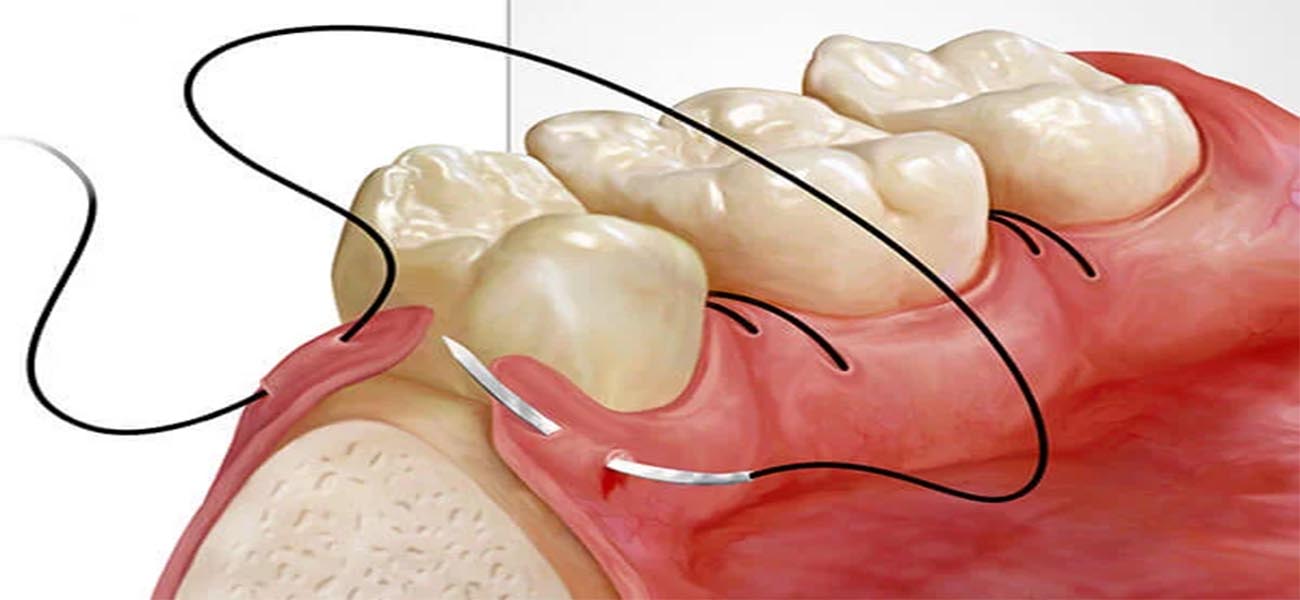

1. درمان بیماریهای لثه

یکی از اصلی ترین خدمات دکتر ندافپور، تشخیص و درمان بیماریهای لثه مانند التهاب لثه، پریودنتیت و دیگر مشکلات مربوط به بافتهای نرم دهان است. ایشان با استفاده از روشهای نوین و تجهیزات پیشرفته، قادر به ارائه درمانهای مؤثر و سریع هستند.